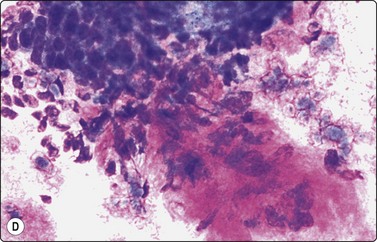

Basal cell carcinoma (Fig. 14.14)8,45-48

Criteria for diagnosis

Tight cell aggregates with sharp outline, smooth edges, often budding,

Palisading of nuclei along the edge of aggregates,

Small cells with scanty cyanophilic cytoplasm; indistinct cell borders,

Small, hyperchromatic, ovoid, overlapping nuclei; indistinct nucleoli,

Stromal material variable.

Most basal cell carcinomas (BCC) are diagnosed clinically. Scrape smears from the surface can provide rapid pretreatment confirmation, of particular importance if non-surgical treatment is considered. If the lesion is ulcerated, any inflammatory debris should be removed prior to vigorous scrapings.8 Non-ulcerated, deeply invasive tumors are suitable for FNB sampling using a thin 25–27-gauge needle.

The most characteristic feature of BCC in smears is the strong cohesiveness of the cells, which remain in well-defined tissue fragments of tightly packed small cells with palisading of nuclei along the edges. The fragments resemble tumor buds seen in tissue sections (Fig. 14.14A). The same pattern was seen in FNB smears from a rare case of distant metastasis to bone from of a large, deeply invasive BCC on the back of an elderly patient (Fig. 14.14B). The cells are small with very scanty cytoplasm and overlapping, ovoid, relatively uniform hyperchromatic nuclei. The chromatin is evenly distributed and nucleoli are inconspicuous. Subtyping of BCC is generally not possible, but stromal material can be prominent in smears from desmoplastic, infiltrating basal cell carcinoma, suggesting a differential diagnosis of chondroid syringoma (Fig. 14.14D).

image image image image

Fig. 14.14 Basal cell carcinoma

(A) Cohesive epithelial fragments with alternating sharp and irregular borders (H&E, IP); (B) Tissue fragments of very cohesive basaloid cells. The fragments have well-defined borders of cells with a tendency to palisading. This smear is a FNB sample from a bone deposit of metastasizing basal cell carcinoma (MGG, HP); (C) Tumor fragment of small, tightly packed cells, FNB smear (H&E, MP); (D) Basal cell carcinoma, infiltrating type; tumor fragment of closely packed small, uniform basal cells and adherent fibrillar fibrous stroma (MGG, LP).

In clinical practice, the main differential is BCC versus actinic keratosis. Christensen et al., in a study of 78 cases, found cytological diagnosis to be highly accurate if samples are adequate.48 In general, the microarchitecture and the predominance of typical basal cells are characteristic of BCC. Cells of actinic keratosis are less cohesive, and show features of dysplastic squamous epithelial cells with more abundant cytoplasm. Cells of non-keratinizing, basaloid squamous cell carcinoma are also less cohesive, larger, some with dense squamoid cytoplasm, some with prominent nucleoli.